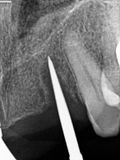

fredlibc | all galleries >> Galleries >> NSankhyan - immediate 11 and 22 > R4.jpg

R4.jpg